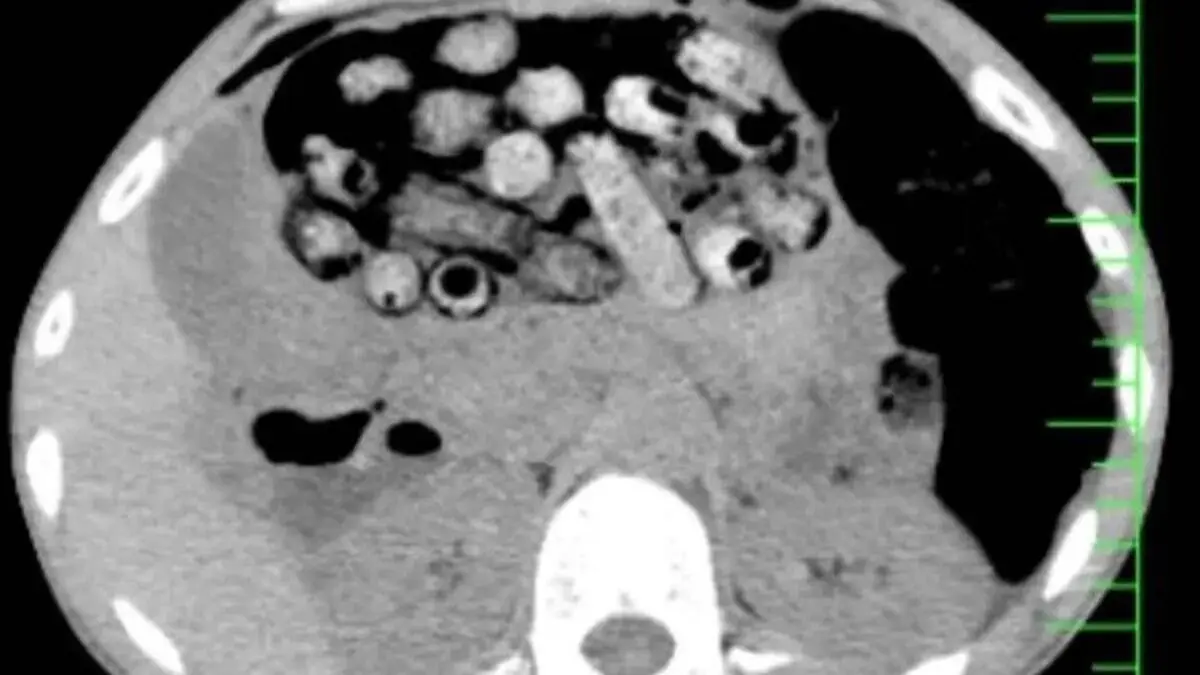

علت مراجعه بیمار مشخص شدبر اساس توضیحات مأمور همراه، این فرد پیش از ورود به بیمارستان، اقدام به بلع چندین بسته محتوی مواد مخدر کرده بود. در تصویربرداریهای انجامشده، تعداد قابلتوجهی بسته درون معده و رودههای کوچک و بزرگ او شناسایی شد.

اقدام فوری برای جلوگیری از بروز خطربه دلیل پتانسیل پارگی بستهها و خطرات جانی جدی، بیمار فوراً به اتاق عمل منتقل گردید. این عمل سخت و فوری از ساعت سه بامداد آغاز شد.

عمل جراحی موفقیتآمیزبه لطف تلاشهای دکتر سامان شیخی ، عضو هیأت علمی گروه جراحی عمومی دانشگاه علوم پزشکی البرز، و همکاری تیمهای اورژانس، تصویربرداری، بیهوشی و جراحی، ۹۰ بسته مواد مخدر از معده و روده بیمار خارج شدند.